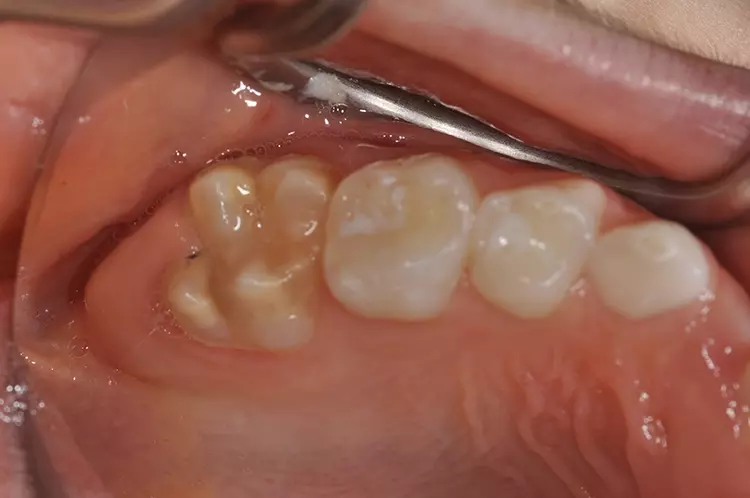

Typisch sind bei der leichten Form der Erkrankung weiße, cremige oder gelblich bis braune Opazitäten (Abb. 1). Im Gegensatz zur Dentalfluorose zeigt sich eine große Variabilität in Form, Farbe und Größe an den Zähnen innerhalb einer Mundhöhle. Bei der schweren Form bricht die Schmelzoberfläche nach dem Durchbruch des Zahnes im okklusalen Kontaktbereich aufgrund der Kaukräfte ein oder die Zähne weisen bereits im Durchbruch Defekte und Hypoplasien auf (Abb. 2).